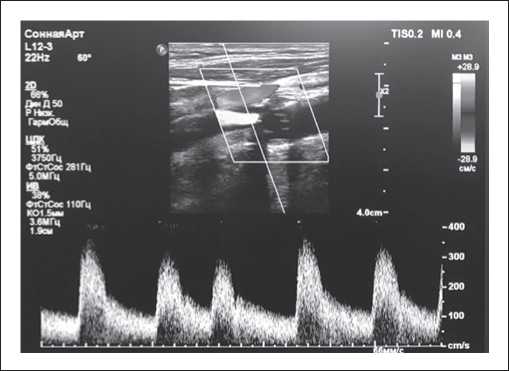

При анализе ЛСК при выполнении УЗДГ БЦС и задней артерии голени в 1ПЭС наблюдалось возрастание ЛСК и объемного кровотока (пропорционально ЛСК) до 40% при «поздней» ЭС и до 58% при «ранней» ЭС по сравнению с параметрами при правильном ритме. Причем наблюдалась отчетливая тенденция: чем раньше систола желудочков ЭС возникала в кардиоцикле, тем большее возрастание ЛСК и объемного кровотока происходило (рисунок 6).

Рисунок 6. УЗДГ БЦС при поздней ЭС.